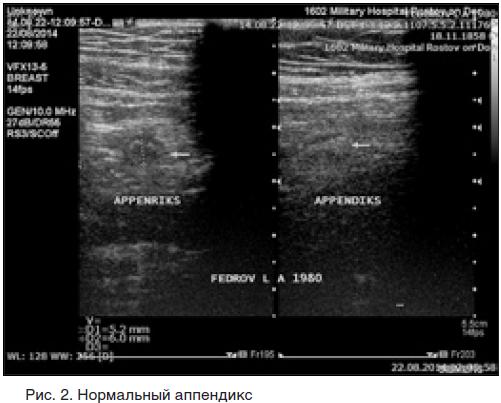

Узи выявит аппендицит 117 фотографий